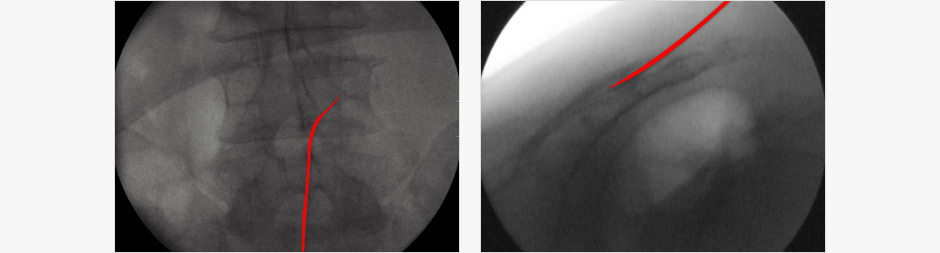

작은 관을 척추 경막외강으로 삽입하여 질환을 일으키는 부위에 직접 약물을 주입하고

유착 등의 방해 요소들을 제거하여 요통이나 방사통증을 제거하는 방법입니다.

가버 라츠(Gabor B. Racz) 박사가 고안해 일명 ‘라츠(Racz)’라고 불리우는 방법으로 미국 등에서 널리 사용되고 있는

방법이며 직경이 약 2mm정도 되는 작은 관을 척추 경막외강으로 삽입하여 질환을 일으키는 부위에 직접 약물을 주입하고 유착 등의 물리적 방해 요소들을 제거하여 요통이나 방사통증을 제거하는 방법입니다.

환자분은 시술하는 동안 엎드려 누워 있는 자세를 취하며 꼬리뼈주변을 국소마취하여 시술합니다.

꼬리뼈를 통해 2mm 관을 삽입하여 통증의 원인 제거 및 신경관의 유착부위 박리를 시행하고

삽입된 관을 통해 약물을

투여함으로써 신경의 부기를 가라 앉히고 염증을 치료하게 됩니다.

영상장치를 사용하여 약물이 들어가는 위치를 정확히 확인하는 장점이 있으며 시술시간은 15~20분 정도로 짧고

통상적으로 시행되던 경막외 신경차단술에 비해서 물리적인 방법을 사용해 유착부위를 확인하고 시술 도중에 박리를

할 수 있는 장점이 있습니다.